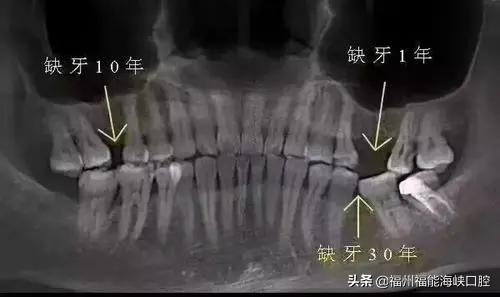

牙齿掉了后的危害

缺牙的危害很多人并没有真切了解过。其实缺牙不但会让吃东西变得不方便,还有更多深层的身体健康方面的影响。

缺一颗牙,会导致旁边的牙齿倒向缺牙处,时间久了相邻的牙齿也会松动掉牙;

缺牙还会让食物咀嚼不充分,出现偏侧咀嚼;

增加肠胃消化负担,导致肠胃变虚弱,营养吸收变差,营养跟不上加速人体衰老。

缺牙的危害,是潜移默化的,因此一定要好好地保护牙齿。